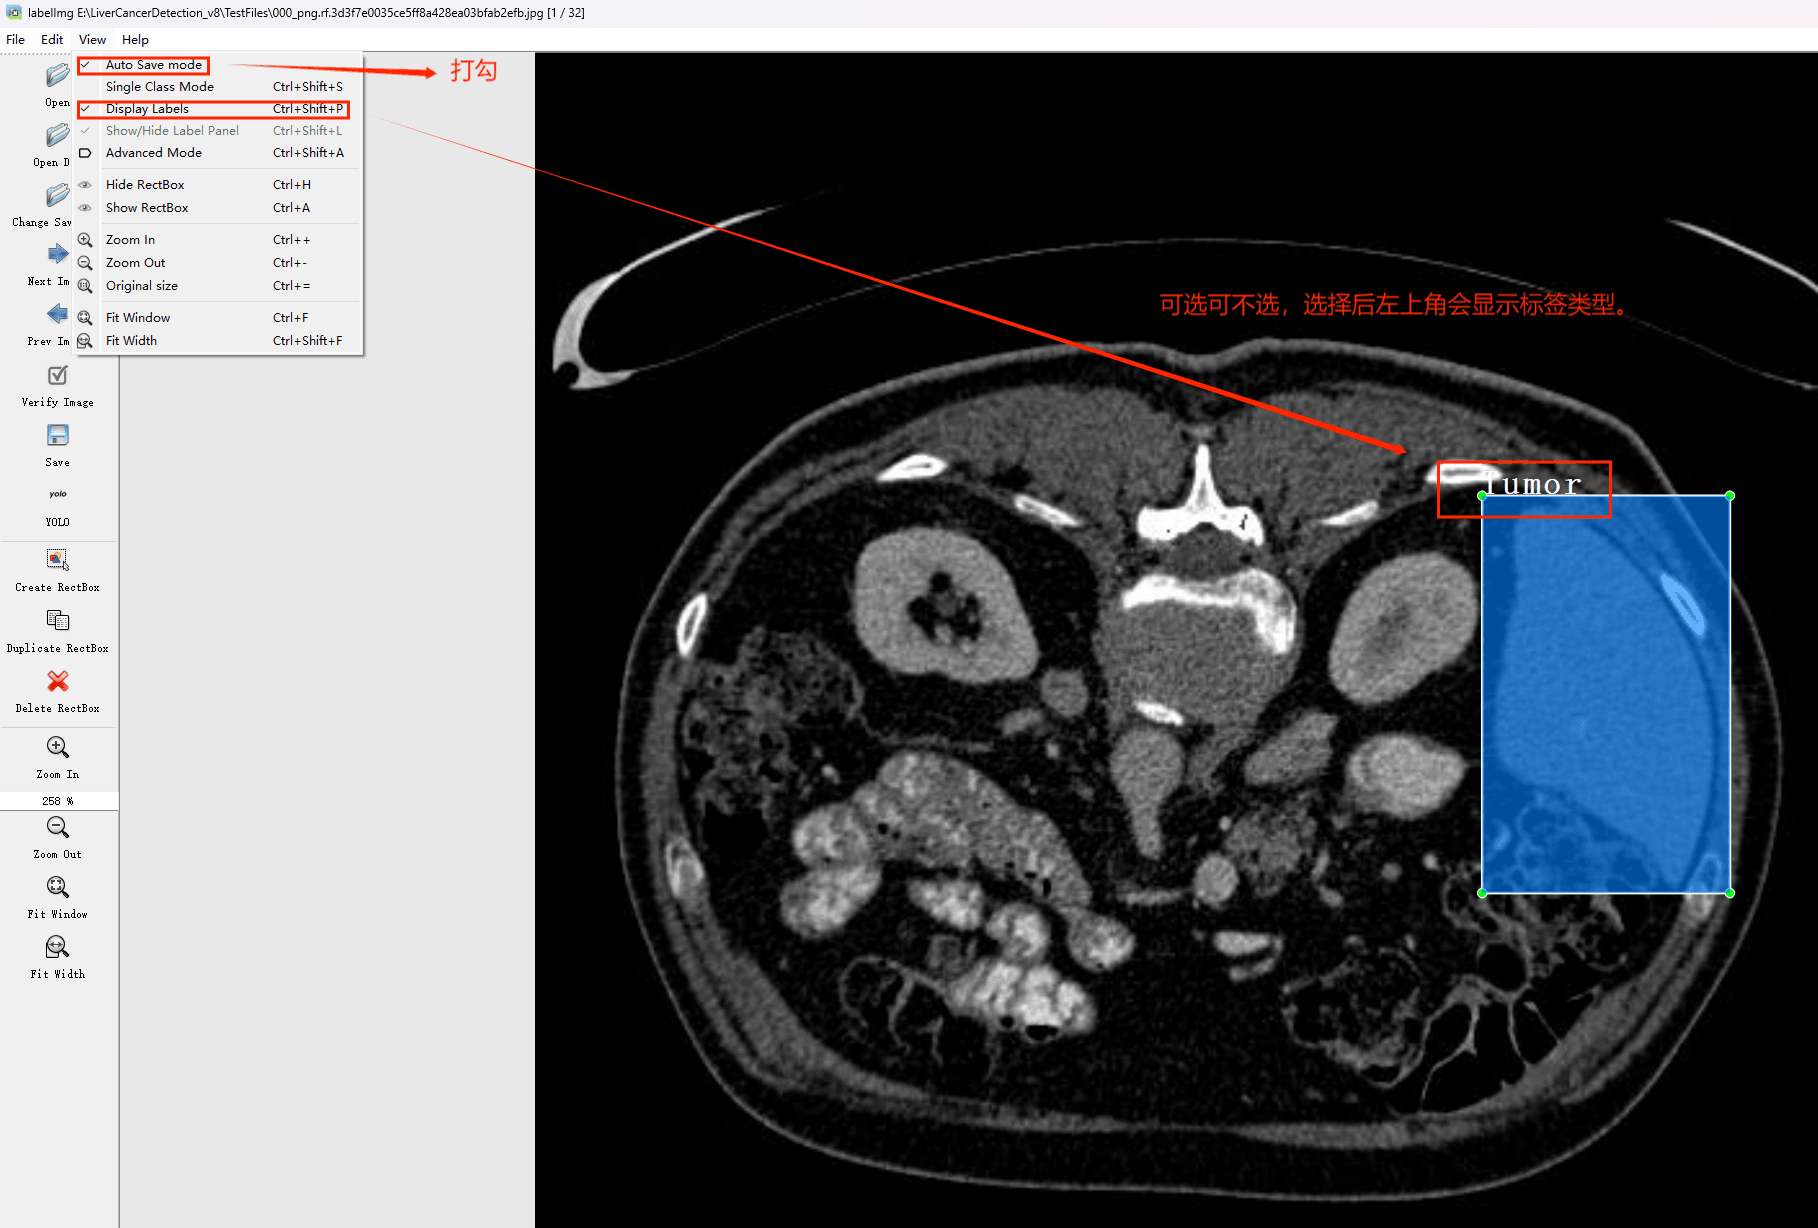

目标检测标注工具

(1)labelimg:开源的图像标注工具,标签可用于分类和目标检测,它是用python写的,并使用Qt作为其图形界面,简单好用(虽然是英文版的)。其注释以 PASCAL VOC格式保存为XML文件,这是ImageNet使用的格式。此外,它还支持 COCO数据集格式。

(2)安装labelimg 在cmd输入以下命令 pip install labelimg -i https://pypi.tuna.tsinghua.edu.cn/simple

初识labelimg

打开后,我们自己设置一下

在View中勾选Auto Save mode

接下来我们打开需要标注的图片文件夹

并设置标注文件保存的目录(上图中的Change Save Dir)

接下来就开始标注,画框,标记目标的label,然后d切换到下一张继续标注,不断重复重复。